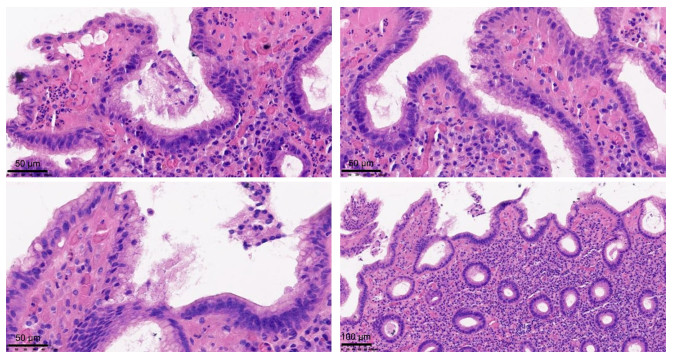

幽门螺旋杆菌感染相关胃炎与自身免疫性胃炎患者病情特征及其鉴别诊断因素分析

华男, 方莹, 严丽园, 陈盼云, 鲁姗姗, 周建波

2026, 24(2): 225-230. doi: 10.16766/j.cnki.issn.1674-4152.004366

9 0

摘要:

目的  分析幽门螺旋杆菌感染相关胃炎与自身免疫性胃炎(AIG)患者病情特征,并探究影响鉴别诊断的因素,为早期识别胃炎类型提供理论依据。  方法  选取2022年9月—2023年12月于宁波大学附属阳明医院治疗的49例幽门螺旋杆菌(Hp)感染相关性胃炎患者为Hp组,选取同期49例自身免疫性胃炎患者为AIG组。收集2组患者的临床资料,并对患者病情特征和鉴别诊断因素进行回顾性分析及总结。  结果  2组患者胃轻瘫主要症状指数(GCSI)、抗内因子抗体(IFA)阳性、胃蛋白酶原Ⅰ(PGⅠ)、胃蛋白酶原Ⅱ(PGⅡ)、PGⅠ/PGⅡ值、胃泌素-17(G-17)比较,差异均有统计学意义(P < 0.05)。Hp相关性胃炎胃镜下可见胃窦黏膜红白相间,以白为主,黏膜下血管透见。AIG胃镜下可见胃底、胃体黏膜变薄,红白相间,以白为主,黏膜下血管透见,可见增生性息肉,而胃窦部相对正常。Hp相关性胃炎组织病理学表现为固有层浅表单核炎性细胞和胃腺颈部中性粒细胞的弥漫性浸润,可见肠型上皮细胞取代泌酸腺黏膜中的上皮细胞。AIG组织病理学表现为固有层中基底层为主的慢性炎性细胞浸润,可见腺上皮的假幽门化生或胰腺腺泡细胞化生。多因素logistic分析显示,PGⅠ/PGⅡ值(OR=0.278,P < 0.001)、G-17(OR=1.268,P=0.005)均为影响Hp相关性胃炎与AIG鉴别诊断的因素。  结论  G-17、PGⅠ/PGⅡ值和组织病理学可用于鉴别Hp相关性胃炎和AIG,以提高诊断的准确性。